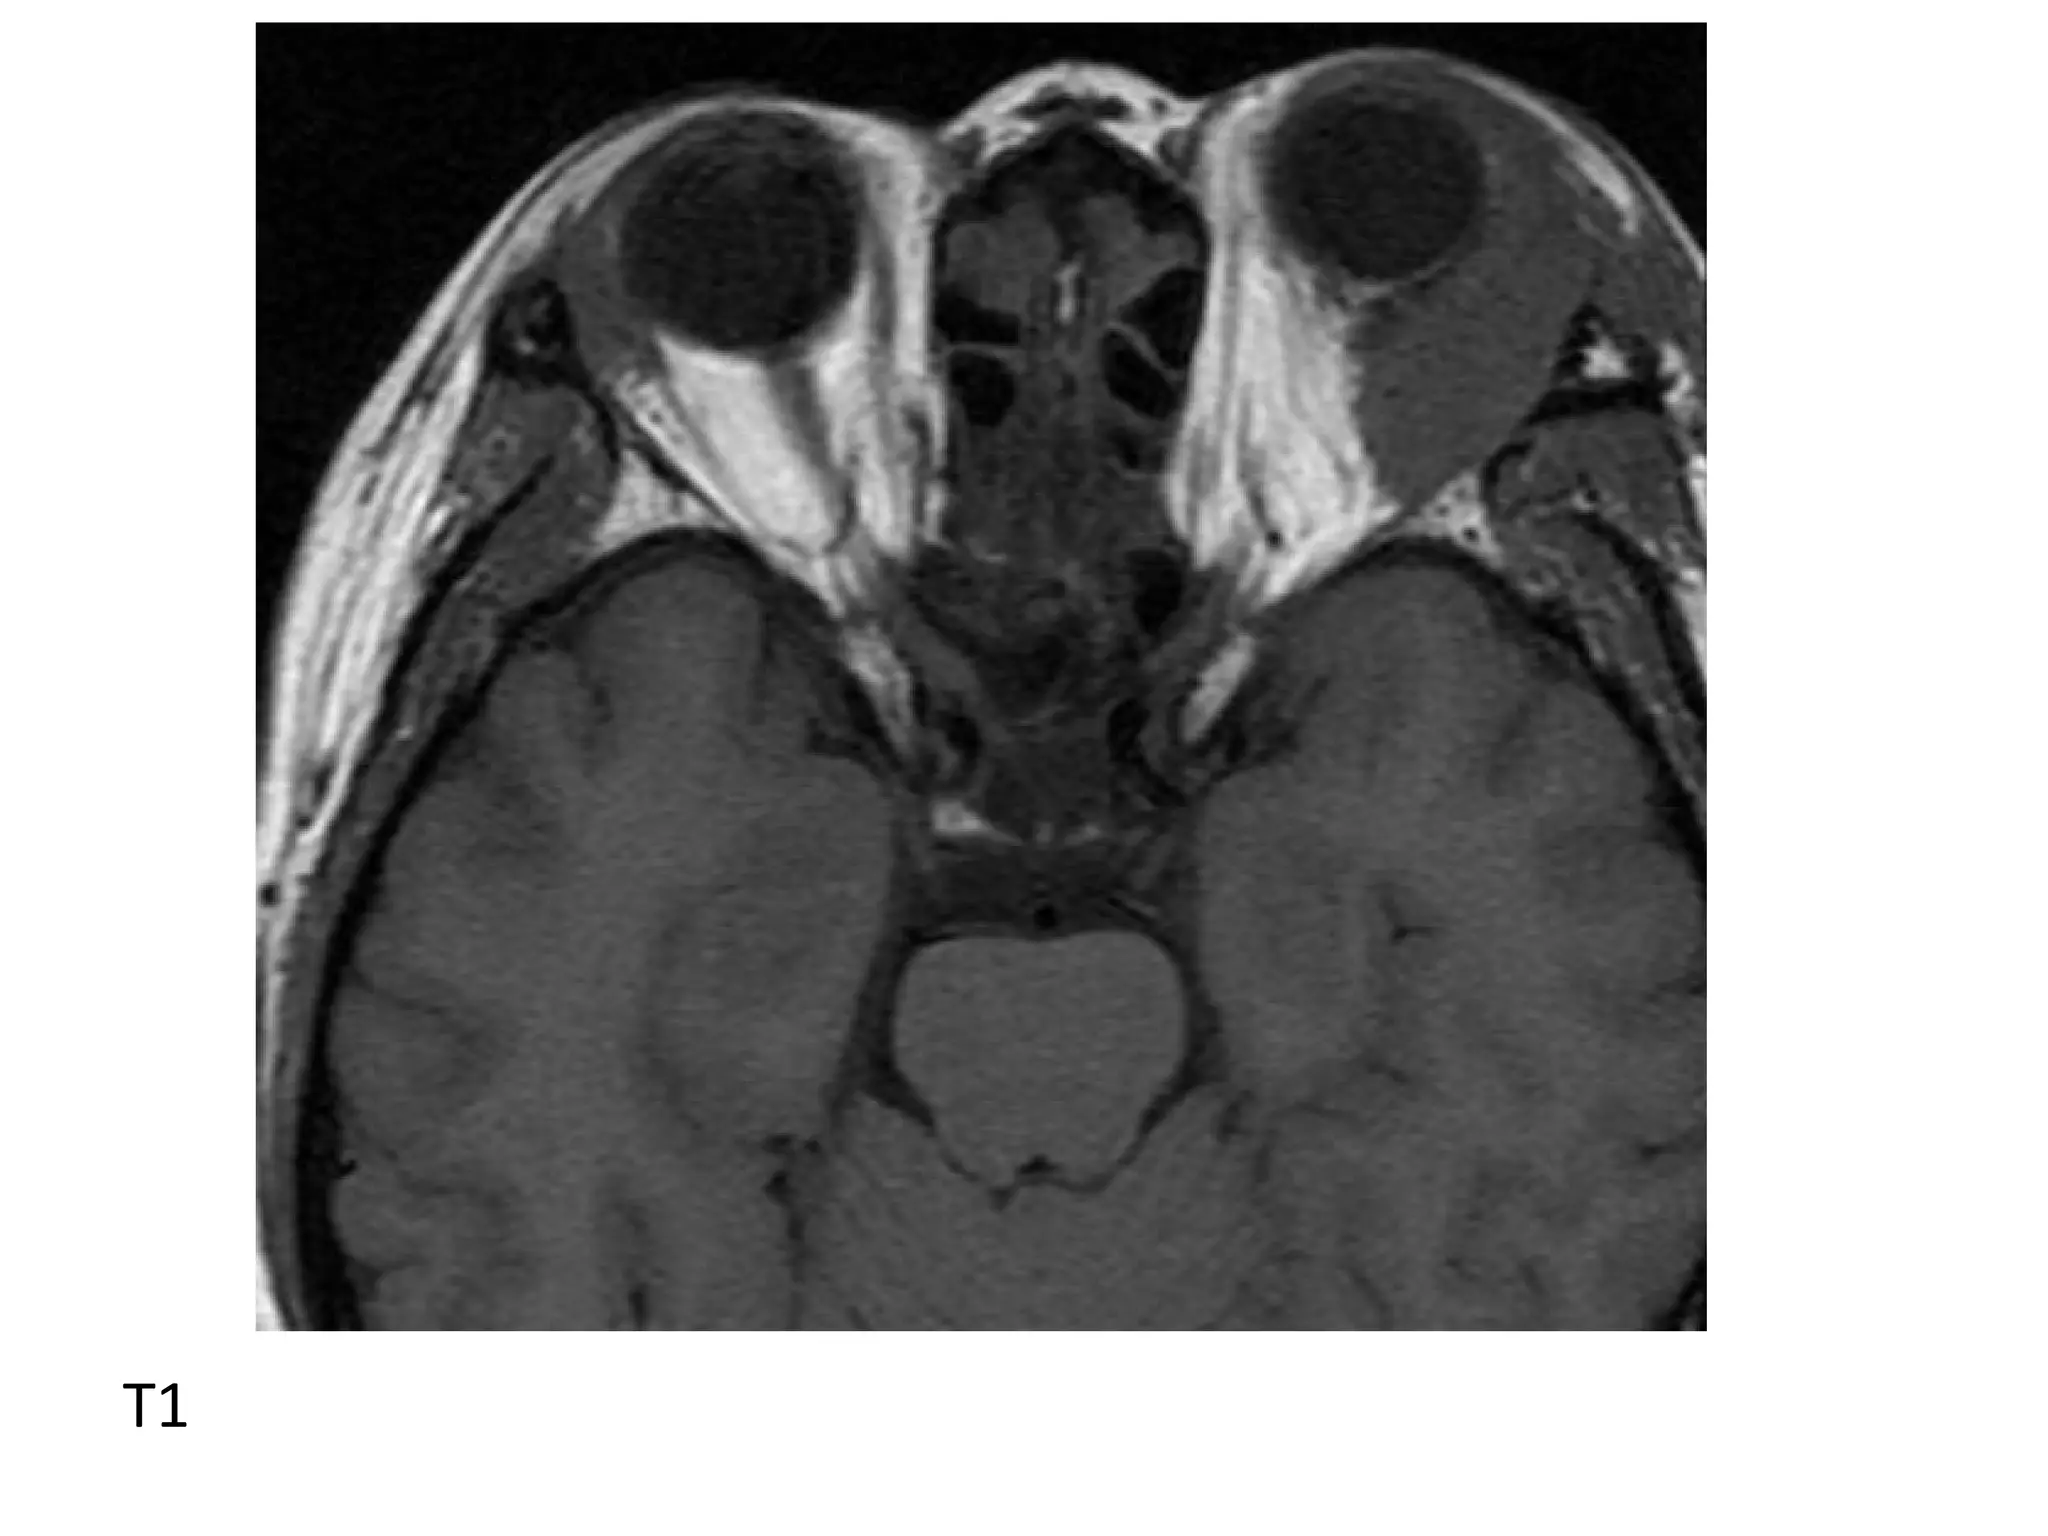

2-MRI :

*T1 : The tumor is slightly/moderately

hyperintense

*T2 : Moderately low intensity

*T1+C : The tumor enhances

T1

T2

T1+C